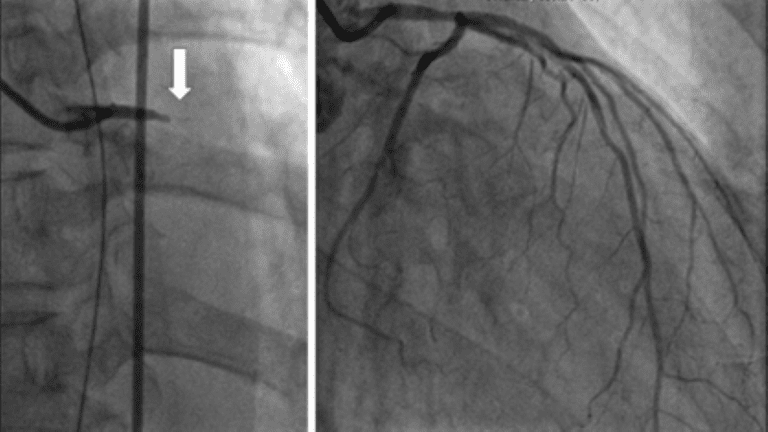

由於王姓男子心電圖呈現疑似急性心肌梗塞,急診室醫師立即啟動心臟科區域聯防平台,聯繫並將病人轉至南門醫院,心臟科陳炳榮主任進行緊急心導管手術後,原本完全阻塞的左側冠狀動脈,立即打通血管後順利恢復血流,病人狀況穩定下來,在加護病房照護期間,陸續移除主動脈內氣球幫浦以及氣管內管,兩天後完全清醒

▲為心臟血管打通前血流完全阻塞(左) ,經治療後心臟血管順利恢復血流(右)。 (圖/北榮新竹分院提供)